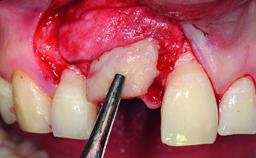

A 23-year-old female, healthy and non-smoking patient had had tooth 11 temporarily restored following a trauma in adolescence. As the patient’s growth had since come to an end and the crown had fractured, she requested an implant-supported restoration of tooth 11. Moreover, the contralateral tooth 21 presented an old composite restoration at the mesial incisal edge. The periodontal tissues were healthy with periodontal probing depth values below 3 mm, but some inflammation was observed around the semi-submerged root of tooth 11.